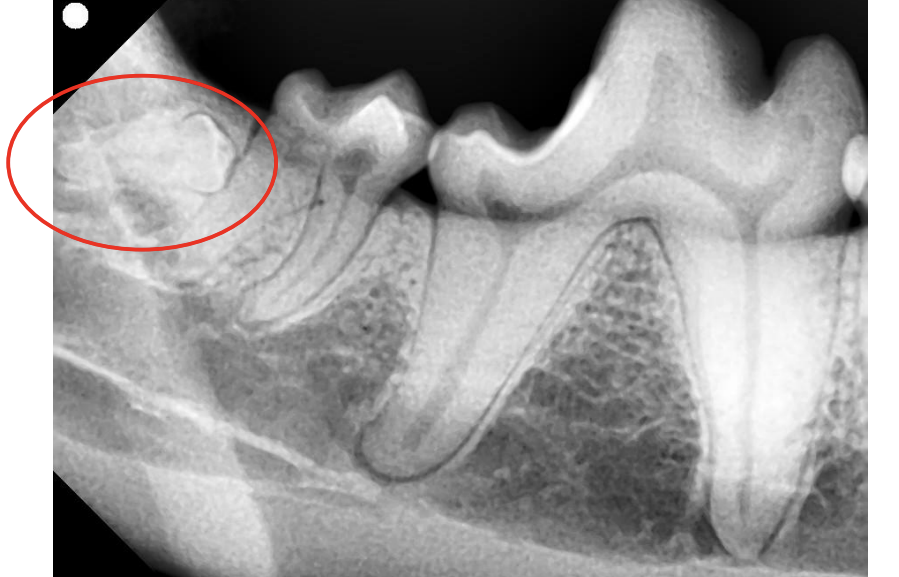

全身麻酔を行い、歯科専用レントゲン撮影と口腔内の評価をしたところ、右下顎第3後臼歯に「埋伏歯(まいふくし)」が確認されました。

赤丸部分 埋伏歯

初期の場合は症状がほとんどないため、埋伏歯があるかどうかは歯科用のレントゲン検査を実施して判明することが多いです。

埋伏歯は口の中を見ただけでは判断が難しいため、歯科レントゲンによる画像診断が不可欠です。歯の位置や形、周囲の骨の状態を確認することで、治療の必要性や方法を判断します。